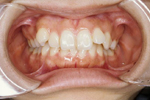

矯正の症例

1) 矯正前の状態

叢生(そうせい…歯がデコボコしたり、重なりあって生えていたりする状態)

開咬(かいこう…奥歯はしっかり噛んでいるが、上下の前歯が噛まずに隙間がある状態)